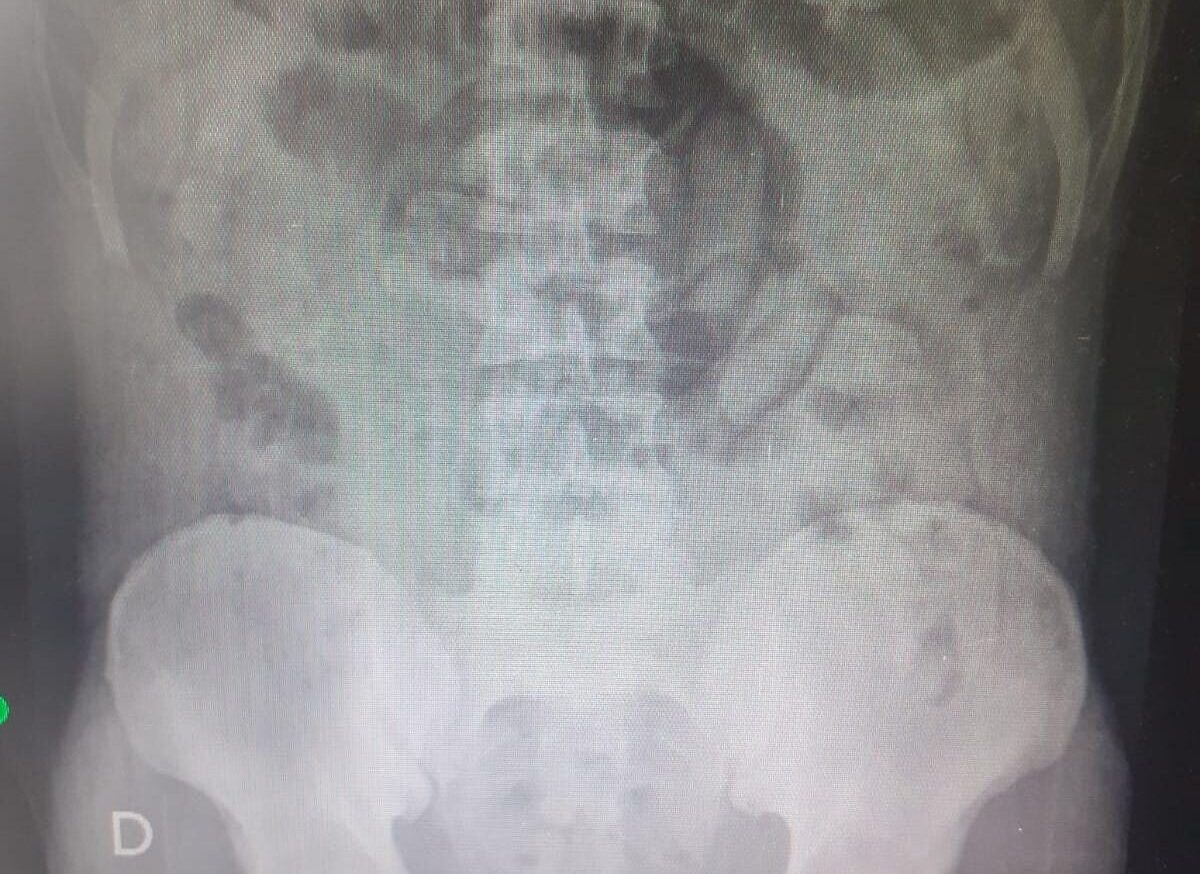

Radiografia confirmou a ingestão das cápsulas de entorpecentes (Foto: Divulgação/PMR)

O estrangeiro foi imediatamente submetido a uma busca pessoal. Os policiais perceberam que sua barriga estava “anormalmente rígida”, o que despertou a suspeita. Sem bagagens além de uma manta, o homem foi questionado, momento em que admitiu ter ingerido cerca de 80 cápsulas de drogas.

Ele disse ainda que nem sabia que tipo de droga estava levando. Com urgência, foi encaminhado à Unidade de Pronto Atendimento (UPA) de Garça, onde foi realizado um exame de raio-x.

O exame confirmou que ele havia ingerido as cápsulas, que continham entorpecentes. O suspeito precisou ser levado para o Hospital de Clínicas (HC) e ficou sob escolta, para série de procedimentos.